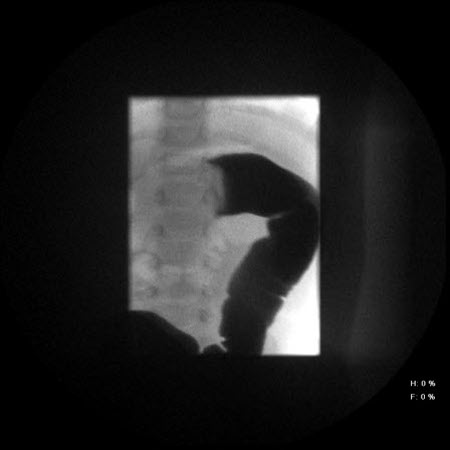

Intussuscepção: radiografia abdominal que mostra a passagem insuficiente de bário no local da obstrução decorrente da intussuscepção

Do acervo de Dr. David J. Hackam